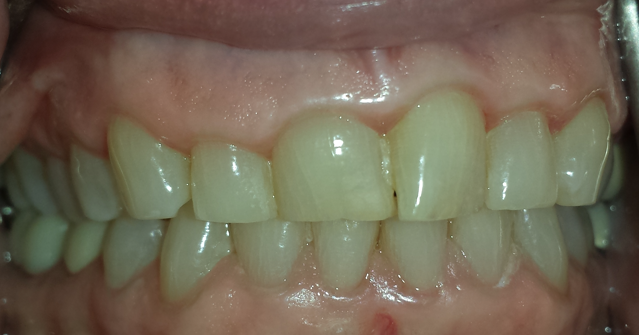

Initial cone beam computed tomography (CBCT) revealed low tongue posture (Figure 1). Figures 2, 3, and 4 show the frontal, maxillary occlusal, and mandibular occlusal views of the dentition, respectively. Clinical examination identified a scalloped tongue with low muscle tone and difficulty achieving palatal suction. Dental findings included upper and lower arch crowding, advanced tooth wear consistent with attrition, a deep skeletal bite evident on cephalometric analysis, and a marked loss of vertical dimension of occlusion (VDO) (Figures 5 and 6).

Figure 5.

(more ...)